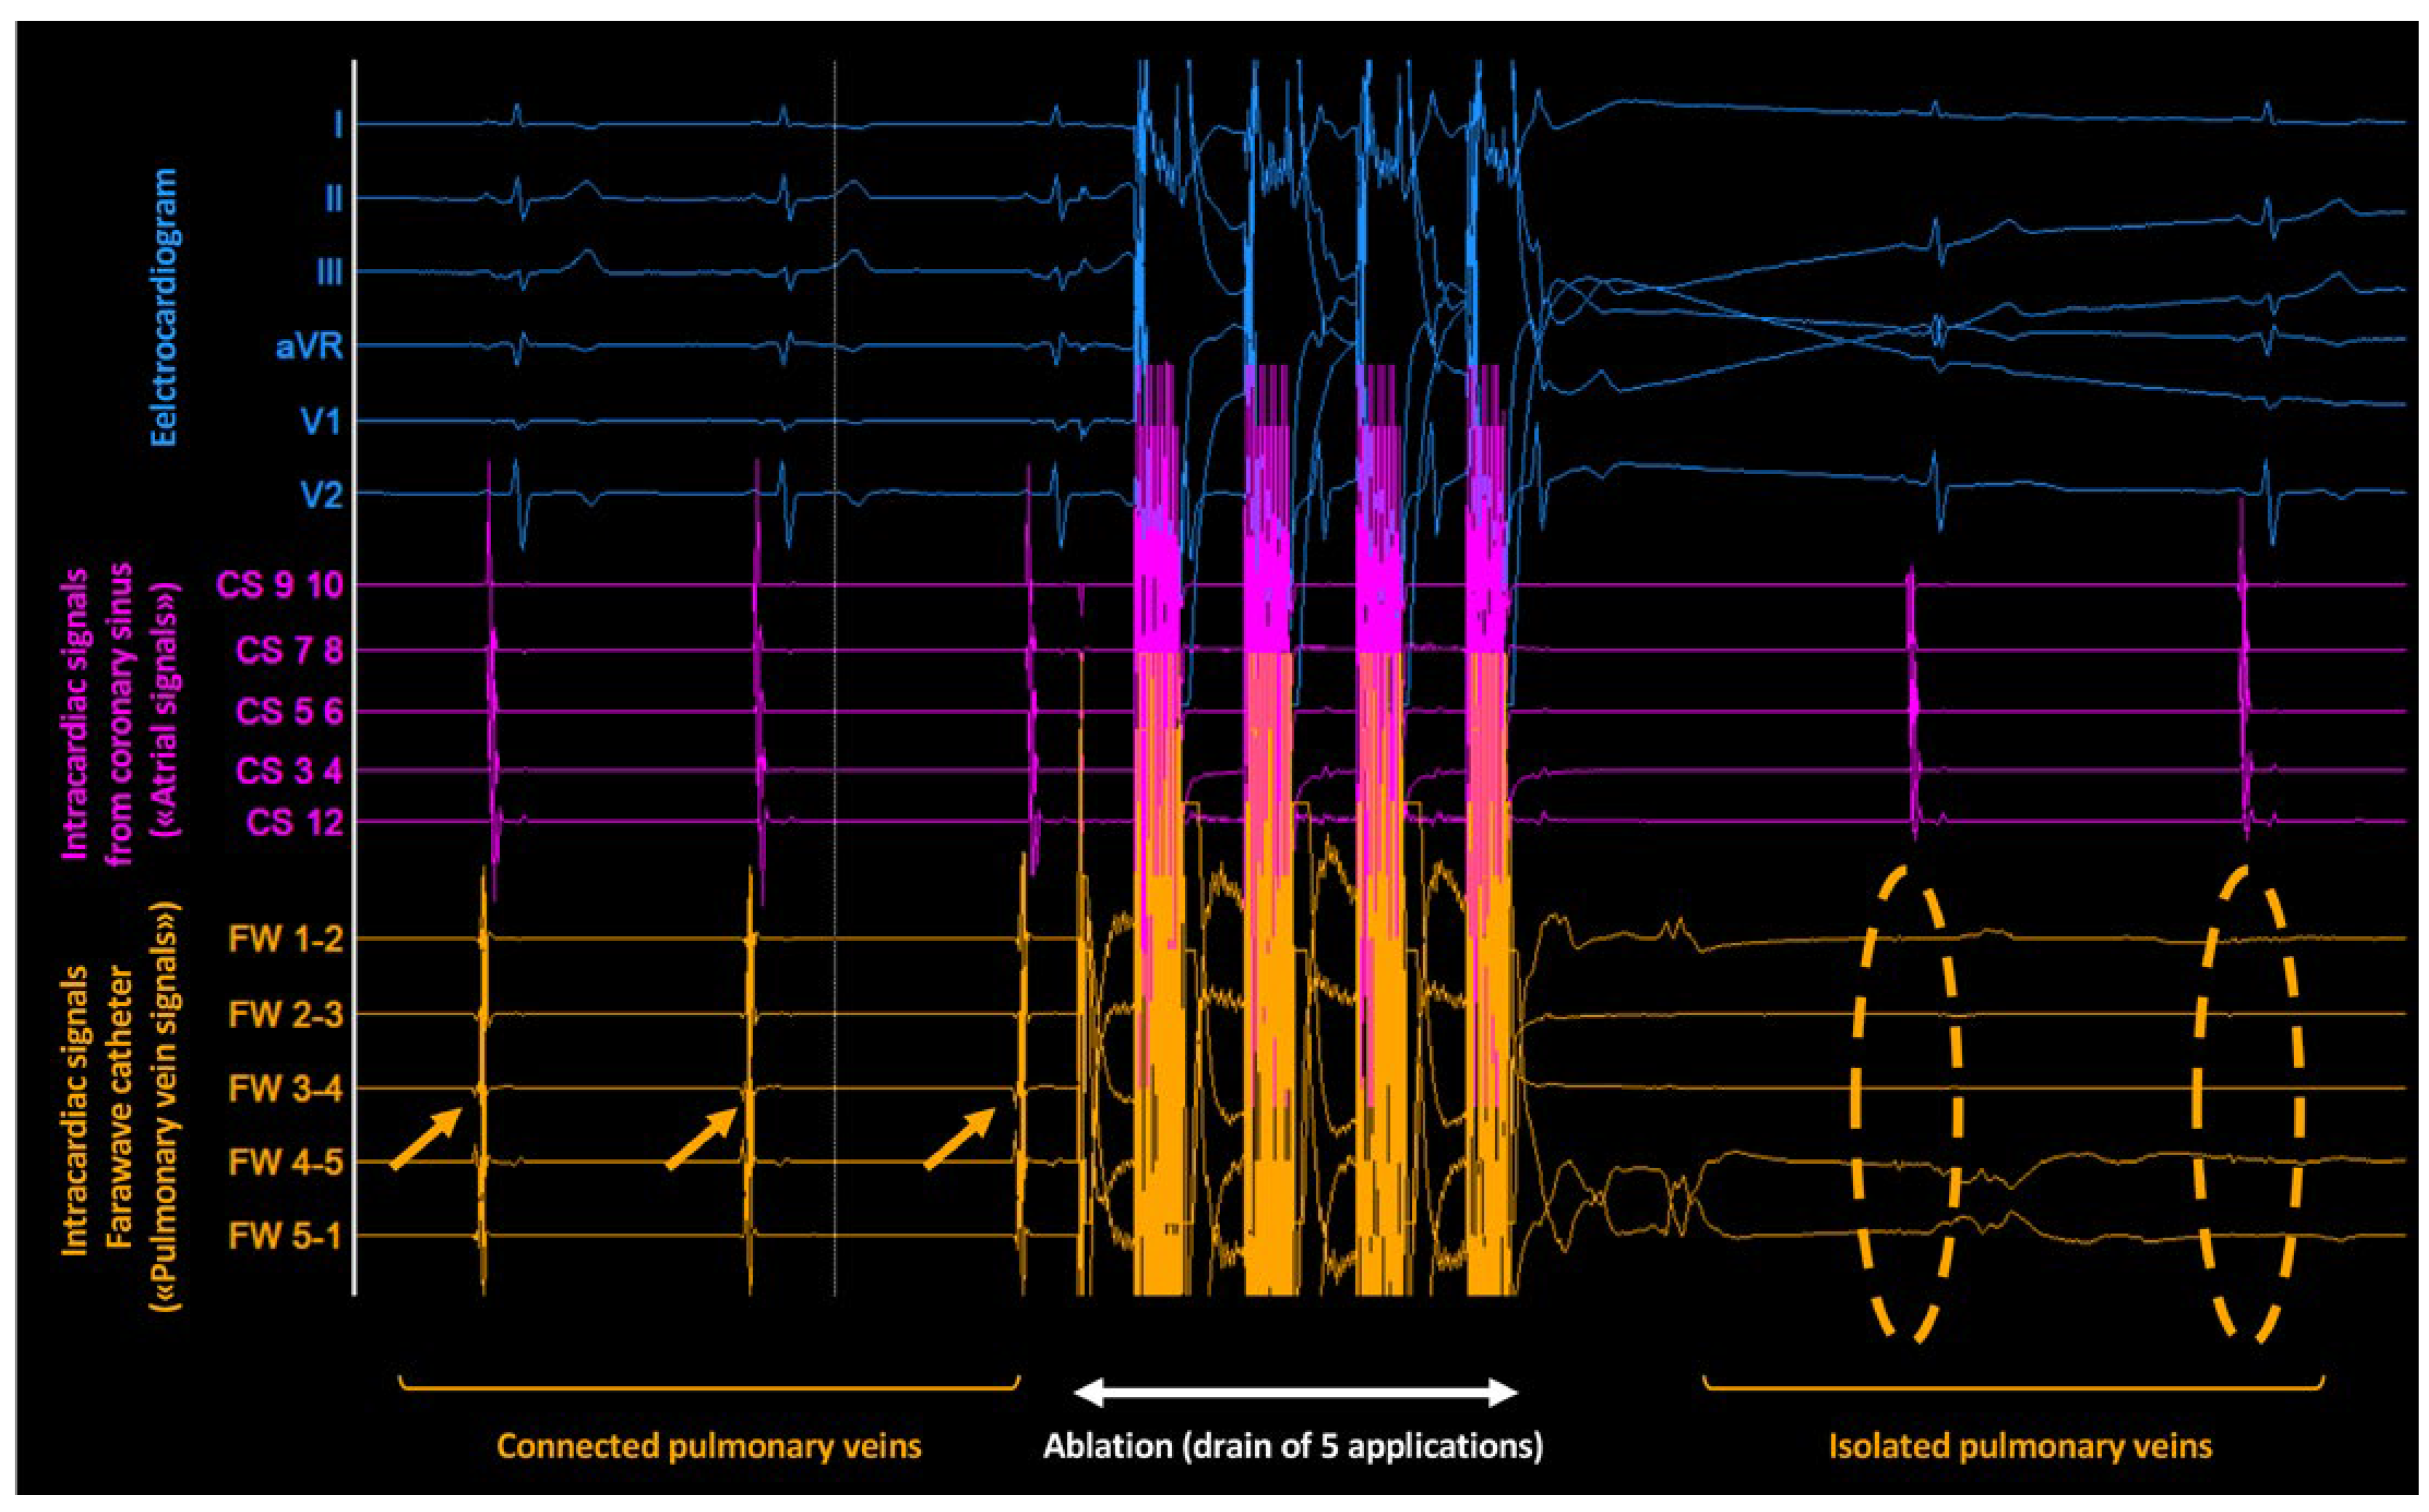

Workflow of a PFA Procedure Using the FARAPULSE™ System

- Kueffer, T.; Baldinger, S.H.; Servatius, H.; Madaffari, A.; Seiler, J.; Mühl, A.; et al. Validation of a multipolar pulsed-field ablation catheter for endpoint assessment in pulmonary vein isolation procedures. Europace 2022, 24, 1248–1255. [Google Scholar] [CrossRef] [PubMed]